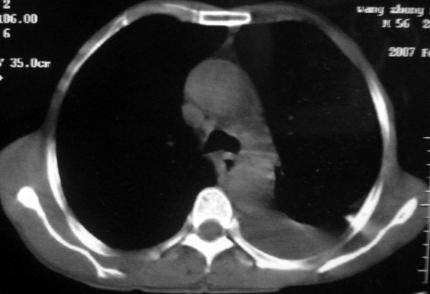

男,54岁,咳嗽,气喘半年,胸痛一月.

血性胸水

支持左肺下叶中心型肺癌(累及舌叶)伴阻塞性肺炎、膨胀不全、胸腔积液、心包少量积液。

左肺下叶中心型肺癌,伴阻塞性肺炎、左胸腔积液、心包少量积液。